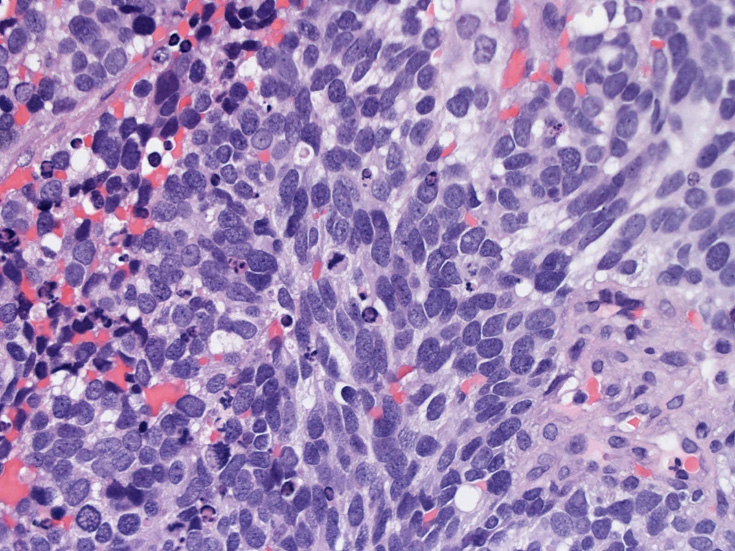

症例--鼻腔腫瘤

30歳代男性 鼻腔腫瘤の生検組織

厳密にはalveolar patternが明らかではなく, solid typeに入る症例かもしれない。異型細胞増殖胞巣が線維化組織に取り囲まれるように散在している. 小さな生検組織のため全体像が不明である。

鼻腔腫瘤生検組織